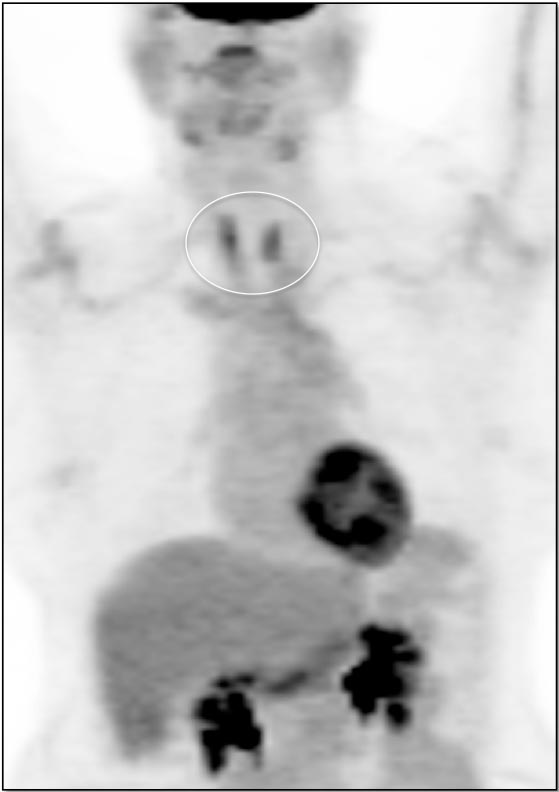

Case 7 (Image 2)

Axial images also demonstrate this diffuse intense uptake. The CT image suggests a slightly enlarged and nodular morphology of the gland.

Case 7 (Image 3)

Given the rather bulbous appearance of the thyroid isthmus, the intensity of the MIP image was manually decreased. This decreased intensity reveals a hypermetabolic nodule masked by the diffuse intense uptake. Biopsy revealed a primary thyroid cancer.